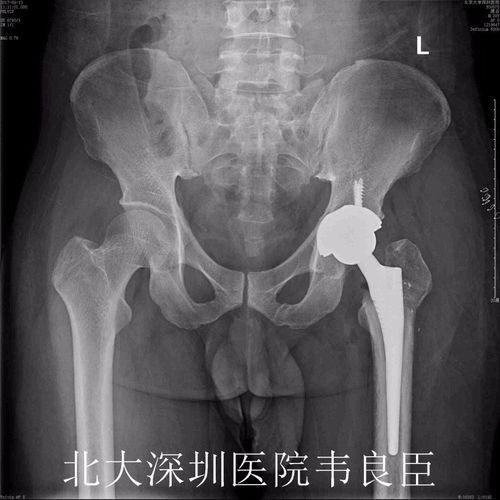

在完成股骨头置换后,医生会继续进行髋臼置换。首先,医生会在髋臼处切开一个小口,然后取出坏死的髋臼部分。接着,医生会植入一个新的髋臼,这个髋臼通常由陶瓷或金属制成。

视频中,我们可以看到医生正在为患者植入新的髋臼。手术过程中,医生需要确保新髋臼与股骨头紧密贴合,以恢复髋关节的正常功能。